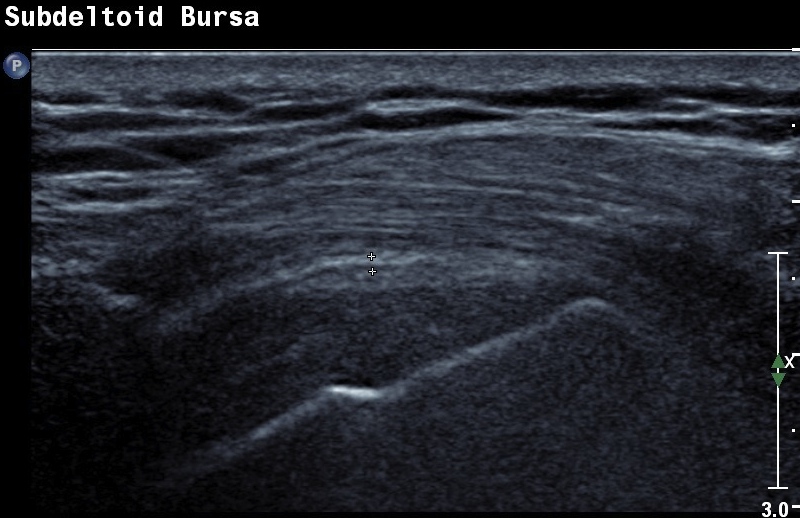

Ultrasound

Dynamic impingement

Bursitis